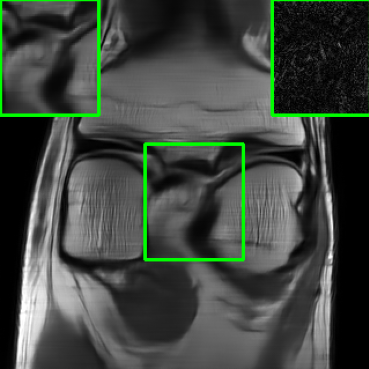

Figure 10 presents visual comparison of image reconstructions and their associated reconstruction errors within a closely examined region. Each image in the figure includes two inset panels in the bottom-left and bottom-right corners. The bottom-left inset panel, enclosed within a green bounding box, serves as a reference for the region of interest in the image. In contrast, the bottom-right inset panel depicts an error map in relation to the ground truth. Notably, our method stands out in its ability to capture more features from the original image, surpassing the performance of alternative methods (as also evident from the reported PSNR values).

V-D2 Robustness to Different Sampling Protocols & Undersampling Rates